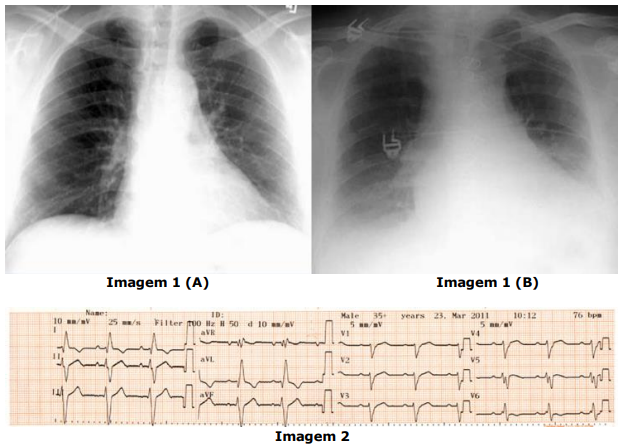

Considerando as imagens abaixo, analise as assertivas a seguir, assinalando V, se

verdadeiras, ou F, se falsas.

( ) A imagem 1 (A) é de um raio-X em projeção posteroanterior (PA) e é a projeção mais adequada para a avaliação do átrio esquerdo e ventrículo direito.

( ) A imagem 1 (B) é de um raio-X em projeção anteroposterior (AP) e é a projeção mais adequada para a avaliação do ventrículo esquerdo.

( ) O raio-X de tórax se tornou obsoleto para avaliação de cardiopatias após o desenvolvimento do ecocardiograma bidimensional, inclusive sendo substituído por ele na avaliação de insuficiência cardíaca pelos critérios de Framingham e de Boston.

( ) A velocidade de registro no eletrocardiograma da imagem 2 é de 50 mm/s.

( ) A amplitude do eletrocardiograma da imagem 2 é de 10 mm/mV.

( ) No eletrocardiograma da imagem 2, a onda P é positiva em DII e aVF e negativa em aVR, sugerindo origem a partir do nó sinusal.

A ordem correta de preenchimento dos parênteses, de cima para baixo, é: